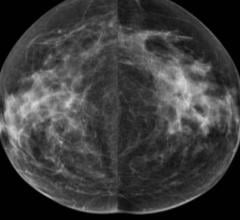

News | Mammography

February 27, 2019 — Radiologists quickly learn to read 3-D mammography more accurately than they read standard 2-D ...

Digital breast tomosynthesis (DBT), also known as 3-D mammography, has come a long way since the first system received U ...